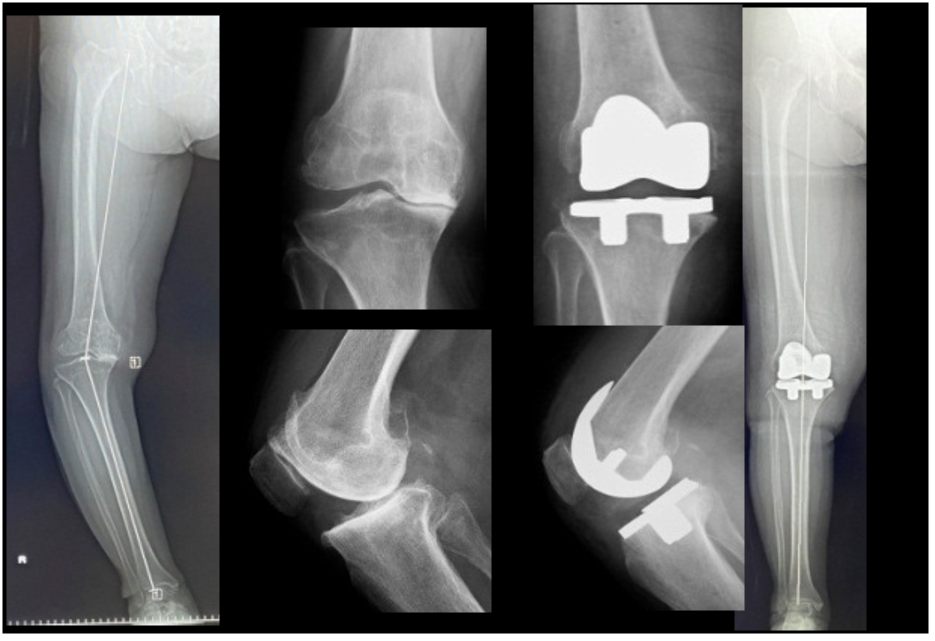

TKAはおもにOA(図2,3)やRA(図4)、UKAは骨壊死(図5)やOAの内側罹患例に行います。左右罹患例には両膝同日手術も施行しています(図3)。手術の目的は除痛、膝関節機能の回復によるADL、QOLの改善です。

人工膝関節は多機種ありますが、当科では自家組織(骨や靭帯)温存に配慮して、主に前十字靭帯のみ切除するCR型を選択し、膝蓋骨は非置換、セメントレス用コンポーネントを用いています(図2)。後療法は両側例でも翌日から離床と荷重を許可し、入院加療は約2週間です。

図2 片側TKA

図3 両側OAに対する両側同日TKA